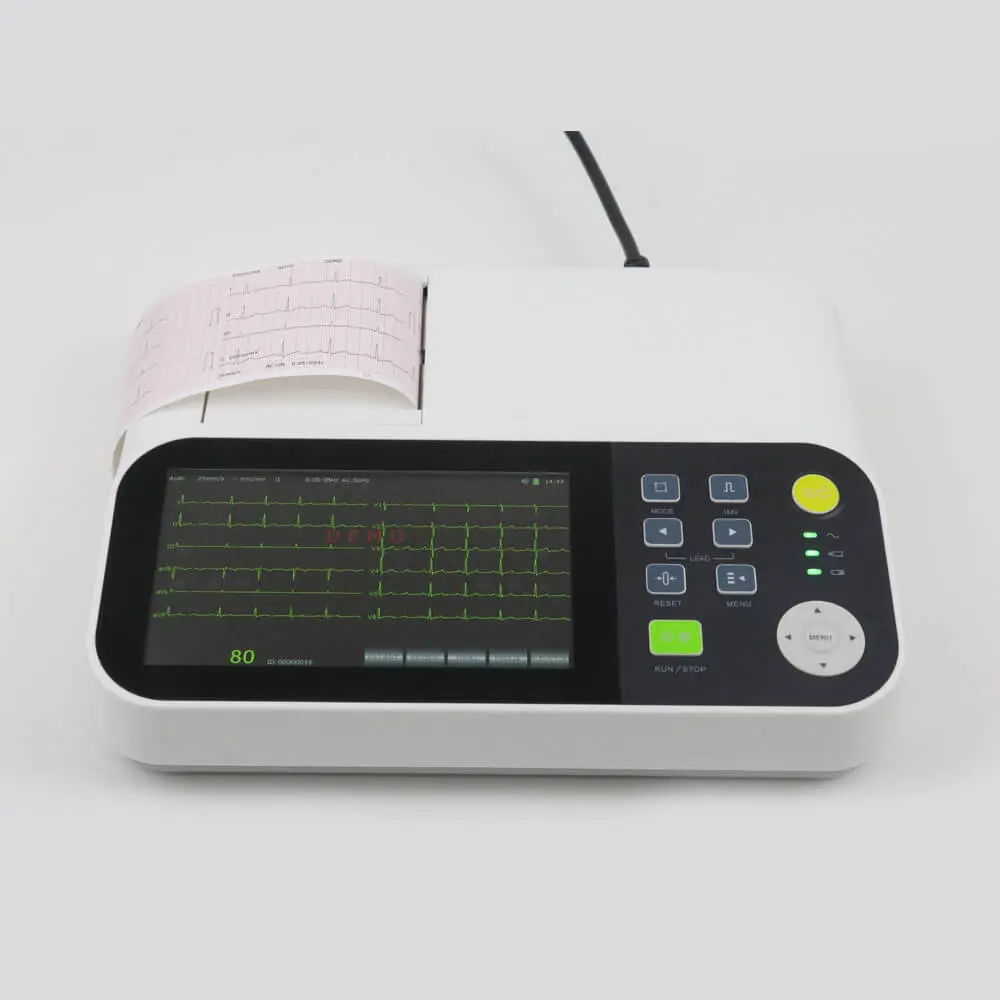

Bionet CardioTouch 3000 12 Channel ECG Machine

Bionet CardioTouch 3000 12 Channel ECG Machine

.jpeg) ECG 12 CHANNEL - MEDEXBIO

ECG 12 CHANNEL - MEDEXBIO

ECG MACHINE 6 CHANNEL - MEDEXBIO

ECG MACHINE 6 CHANNEL - MEDEXBIO

ECG MACHINE 12 CHANNNEL - INDIAN BRAND

ECG MACHINE 12 CHANNNEL - INDIAN BRAND

Digital 6 Channel ECG Machine

Digital 6 Channel ECG Machine

Yonker 7inch display 3 channel ECG Machine with touch screen

Yonker 7inch display 3 channel ECG Machine with touch screen

3 Channel 7 Inch Touch Screen Portable Electrocardiograph ECG Machine

3 Channel 7 Inch Touch Screen Portable Electrocardiograph ECG Machine

Zoncare 12 Channel ECG Machine

Zoncare 12 Channel ECG Machine

Edan ECG Machine SE-601 Series 6-Channel ECG

Edan ECG Machine SE-601 Series 6-Channel ECG

Yonker 7inch Display 3 Channel ECG Machine With Touch Screen

Yonker 7inch Display 3 Channel ECG Machine With Touch Screen

DAWEI 12Channel ECG Machine

DAWEI 12Channel ECG Machine

Dawei ECG Machine 3 Channel

Dawei ECG Machine 3 Channel

.jpeg) Comen – 12 Channel ECG Machine, CM1200

Comen – 12 Channel ECG Machine, CM1200

ECG 1200G – Contec

ECG 1200G – Contec

ECG 1212G – Contec

ECG 1212G – Contec

YKD MED ECG 3 CHANNEL

YKD MED ECG 3 CHANNEL

ECG 12 CHANNEL 3A CANADA

ECG 12 CHANNEL 3A CANADA

ECG Machine - 3 Channels

ECG Machine - 3 Channels